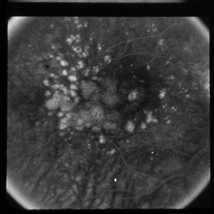

Furthermore, generated images from FA images are presented in Fig. 6 and Fig. 7. Results in the images are nearly identical to the original images, because original networks are applied to stylize color images. However, six generated images contain more concise features than the original ones, which helps ophthalmologists make better judgments. Therefore, this style transferring networks can fulfill edge sharpening and enhancement of contrast. No matter which kinds of images are generated, advanced features in new disease images still exist. Furthermore, analyses of image performance by EyeNet and CAMs for prediction are presented in a later section.

Figure 6: Three FA fundus images with symptom of drusen and corresponding generated images. (a), (b), (c) Original images. (d), (e), (f) Generated images.

Figure 7: Three FA fundus images with symptom of GA and corresponding generated images. (a), (b), (c) Original images. (d), (e), (f) Generated images.